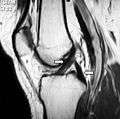

Magnetic resonance imaging evaluation demonstrating normal signal of both anterior and posterior cruciate ligaments (arrows).- Anterior view of knee.